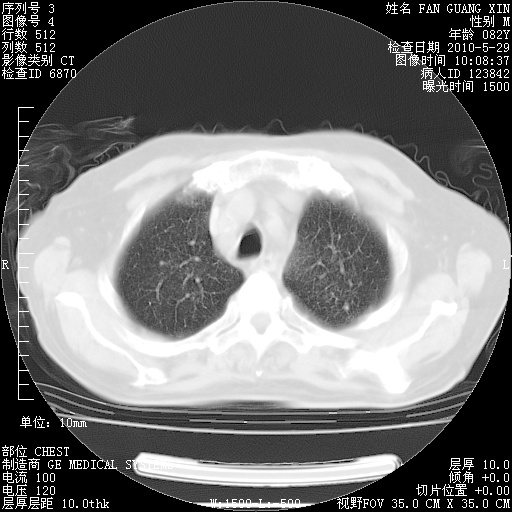

再治疗10天后的肺部CT

再治疗10天后的肺部CT 纵膈窗

阅读此次胸部CT,肺间质渗出性改变较入院时有吸收。目前从体温、白细胞、中性分叶明显增高,肯定存在细菌感染(发生医院感染哦,若无消化道及泌尿系统等感染的依据,肺部感染可能大)。若你院头孢哌酮舒巴坦钠耐药率较高,同意你的方案,若48小时体温仍高,可考虑使用碳青霉稀类抗菌药物,同时可予超声雾化、注意滴数时加大液体量。白蛋白33.30g/L较低哦,需加强营养等支持治疗。